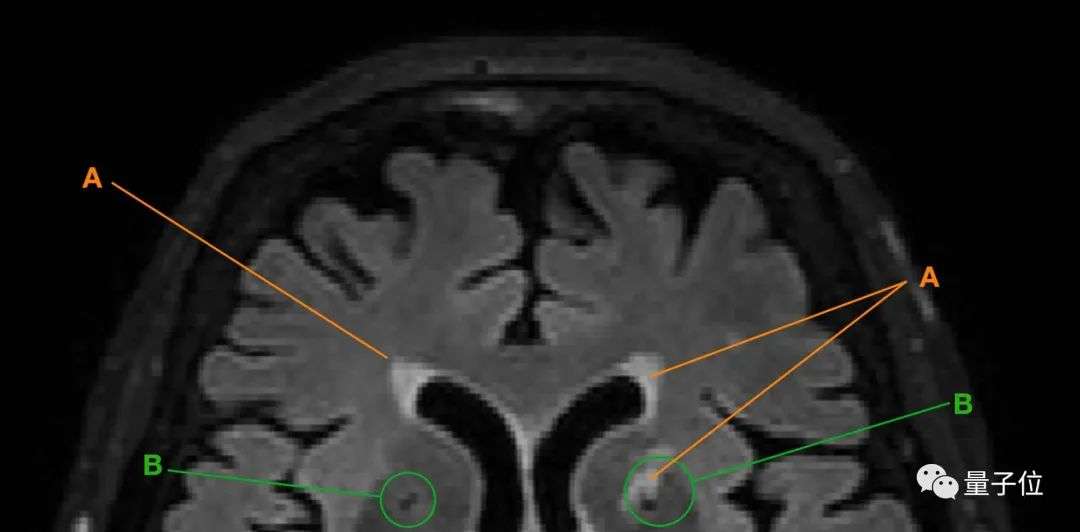

△A为脑白质高信号;B为腔隙

以上两种现象都是脑小血管病(CSVD)的主要表现。

这种疾病在老年人群体中高发,会表现出情感障碍、认知功能下降等症状,

也就是说,当老人的大脑中出现脑白质高信号、腔隙变多变大等情况,就意味着老人的大脑可能在发生退化。